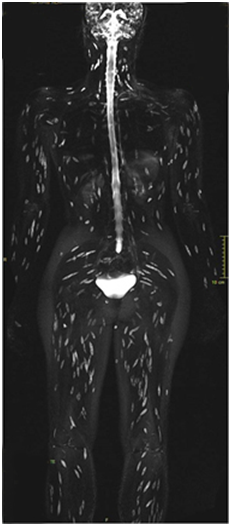

Orthopaedic colleague was consulted for thigh pain and Magnetic Resonance Imaging (MRI) was suggested for recurrent pain and low grade fever. MRI of both thigh regions revealed multiple tiny hyper intense lesions with perilesional edema and rim enhancement in T2 weighted images, consistent with cysticercosis lesions. A whole body MRI showed multiple such lesions all over the body (Figure 4).

Figure 4 A whole body MRI image showing the typical rice grain likes lesions all over the body- typical 'starry sky' appearance seen in disseminated Cysticercosis.

Computed tomography (CT) scans and Magnetic Resonance Imaging (MRI) are useful adjuvants in anatomical localization of the disease. MRI is more sensitive than CT as it identifies live forms, scolex and the response to treatment. Non enhanced CT scans of muscles can show innumerable cysts standing out contrasting against the background of muscle mass in which they are embedded.5 Cysticercosis is seen as a cystic lesion that appears hypo intense on T1weighted and hyper intense on T2 weighted images. Peripheral rim enhancement of the cyst wall is commonly due to reactive edema. Cysts within the muscles are arranged in the direction of the muscle fibers. Within the hyper intense cyst, the scolex is appreciated as a tiny hypo intense speck.7 In our patient the MRI scan had a typical ‘starry sky’ appearance but did not reveal any calcified foci in muscles.